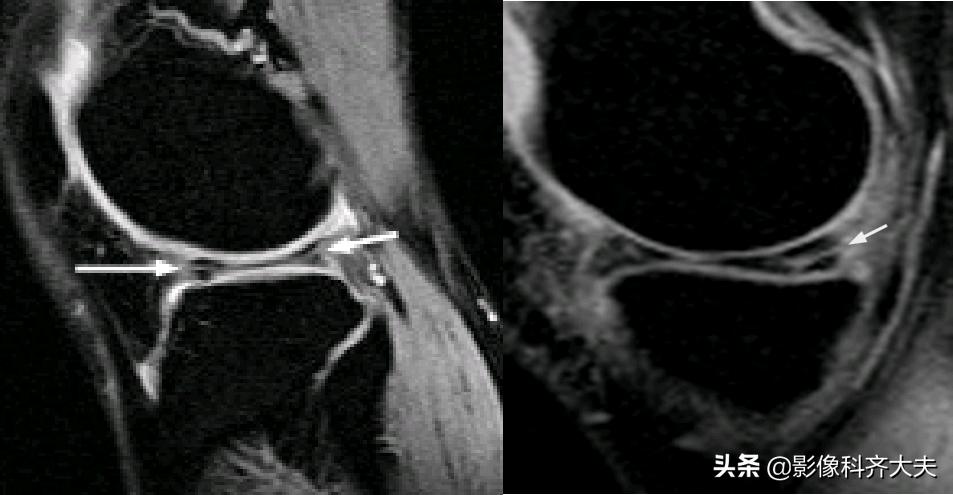

容易误诊为半月板损伤的正常解剖结构

关节内气体伪影:

内侧半月板后角上隐窝: